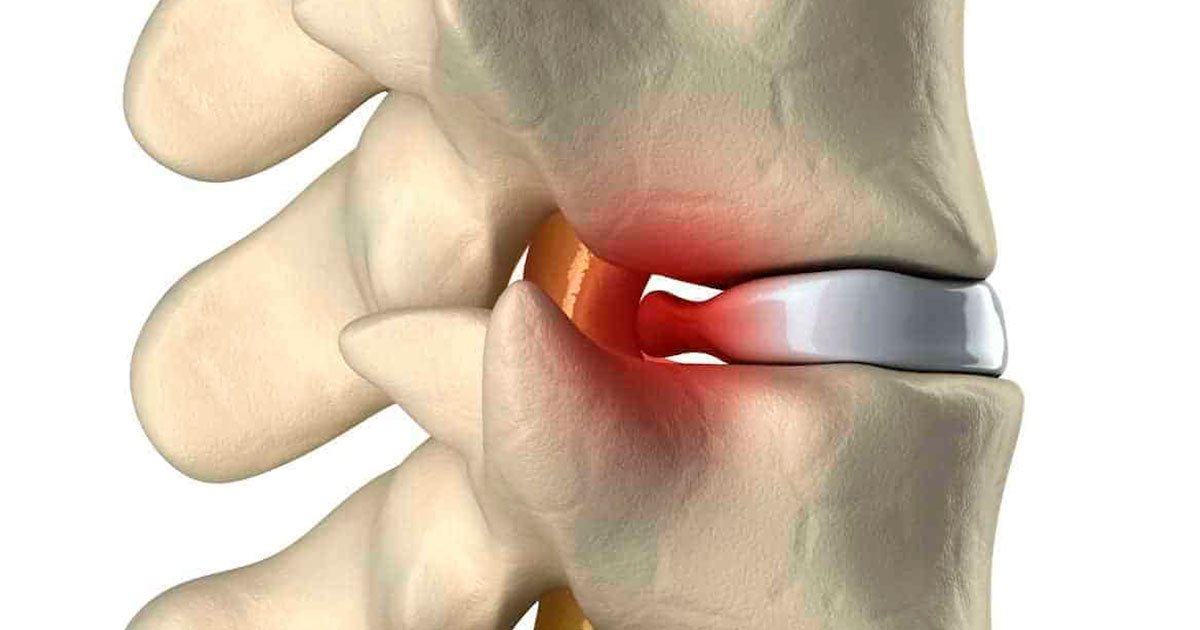

Para a gente entender direitinho, vamos imaginar a nossa coluna como uma pilha de tijolos (as vértebras) com “almofadinhas” entre eles (os discos intervertebrais). Essas almofadinhas são essenciais, agindo como amortecedores, dando flexibilidade e protegendo a coluna.

A hérnia acontece quando uma dessas almofadinhas, por algum motivo – seja por sobrecarga, má postura ou até um movimento brusco –, se desgasta ou se rompe. Aí, parte do seu conteúdo gelatinoso extravasa, e, adivinhe, pode apertar um nervo que está passando ali perto. É essa compressão que causa aquela dor que a gente tanto teme, muitas vezes irradiando para outras partes do corpo.

Os sintomas variam bastante, dependendo de onde a hérnia está localizada. Se for na região lombar, você sente aquela dor chata nas costas que pode descer pela perna, com formigamento ou até fraqueza no pé, um verdadeiro tratamento para dor lombar vira prioridade. Já na cervical, a dor pode ir para o braço, ombro e pescoço, acompanhada de dormência ou perda de força na mão.